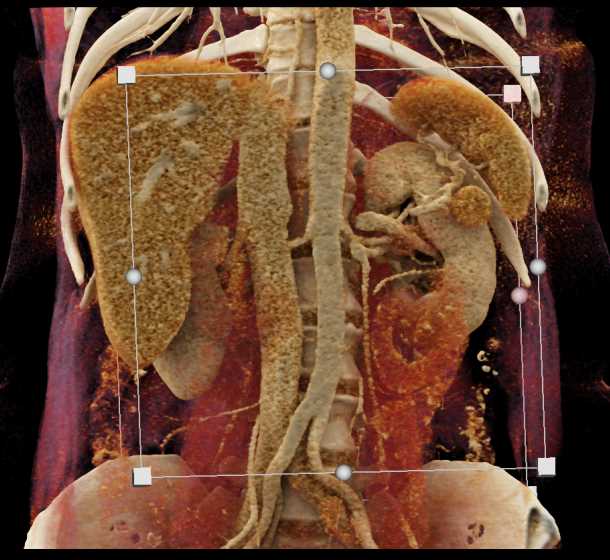

CASE NUMBER 1,519

Gaucher's Spleen